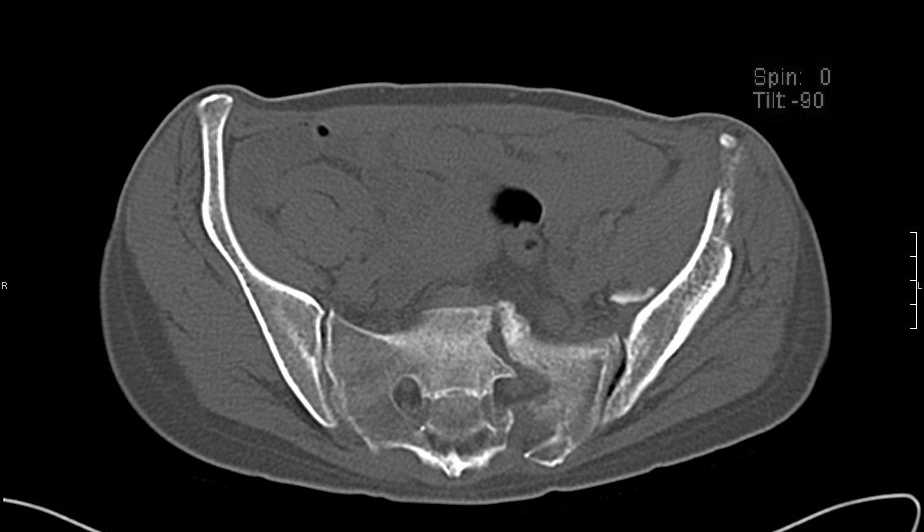

Больная 43 года (промышленный альпинист), 28.07.08 в результате падения с 5 этажа получила политравму: Перелом свода и основания черепа. Вертикально-нестабильное повреждение таза, осложнённое разрывом мочевого пузыря. Чрезвертельный перелом левого бедра. Перелом правой таранной кости, переломовывих правой кубовидной кости. Тупая травма живота, разрыв печени, ушиб почек. Забрюшинная гематома. В день травмы - лапаротомия, ушивание ран печени. Разрыв мочевого пузыря не диагностирован. Течение болезни осложнилось развитием мочевого затёка и обширной пред- и забрюшинной флегмоны, сформировался свищ мочевого пузыря. 19.8.2008 вскрытие, дренировние флегмоны, ревизия мочевого пузыря, обтурация мочевого свища (свищ закрылся в октябре), 1.10.2008 некрэктомия, пластика по Шеде-Лидскому правой кубовидной кости. По результатам КТ диагностирован рак правой почки (диагностическая находка), 8.10.2008 нефрэктомия справа. Переломы велись консервативно. Имеется вертикальное смещение левой половины таза с выраженным отведением крыла (клинически подвижности нет), несросшийся низкий двухколонный перелом левой вертлужной впадины с потерей конгруэнтности, укорочение около5 см, застарелый разрыв лонного сочленения, неправильно сросшиеся переломы обеих ветвей правой лонной кости с укорочением, патологическая подвижность лоно-седалищного фрагмента слева. Правая нижняя конечность неопорна, несмотря на то, что лежа прямую ногу поднимает, ходит на левой ноге (ортопедическая обувь) с костылями, справа тазобедренный ортез. Седалищные нервы работают.Урологи отпустили больную на 6 мес.